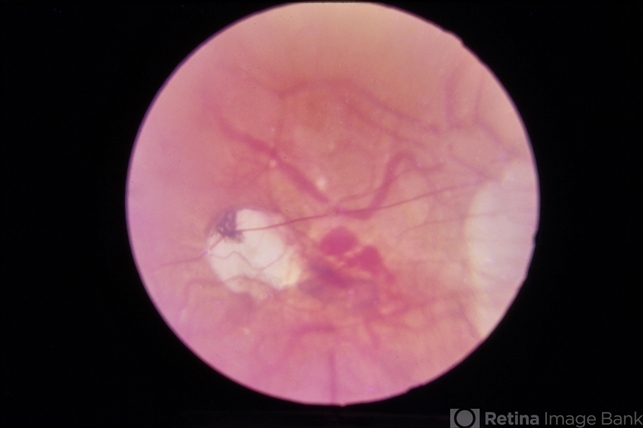

- Hemorrhaging in macula due to myopia.